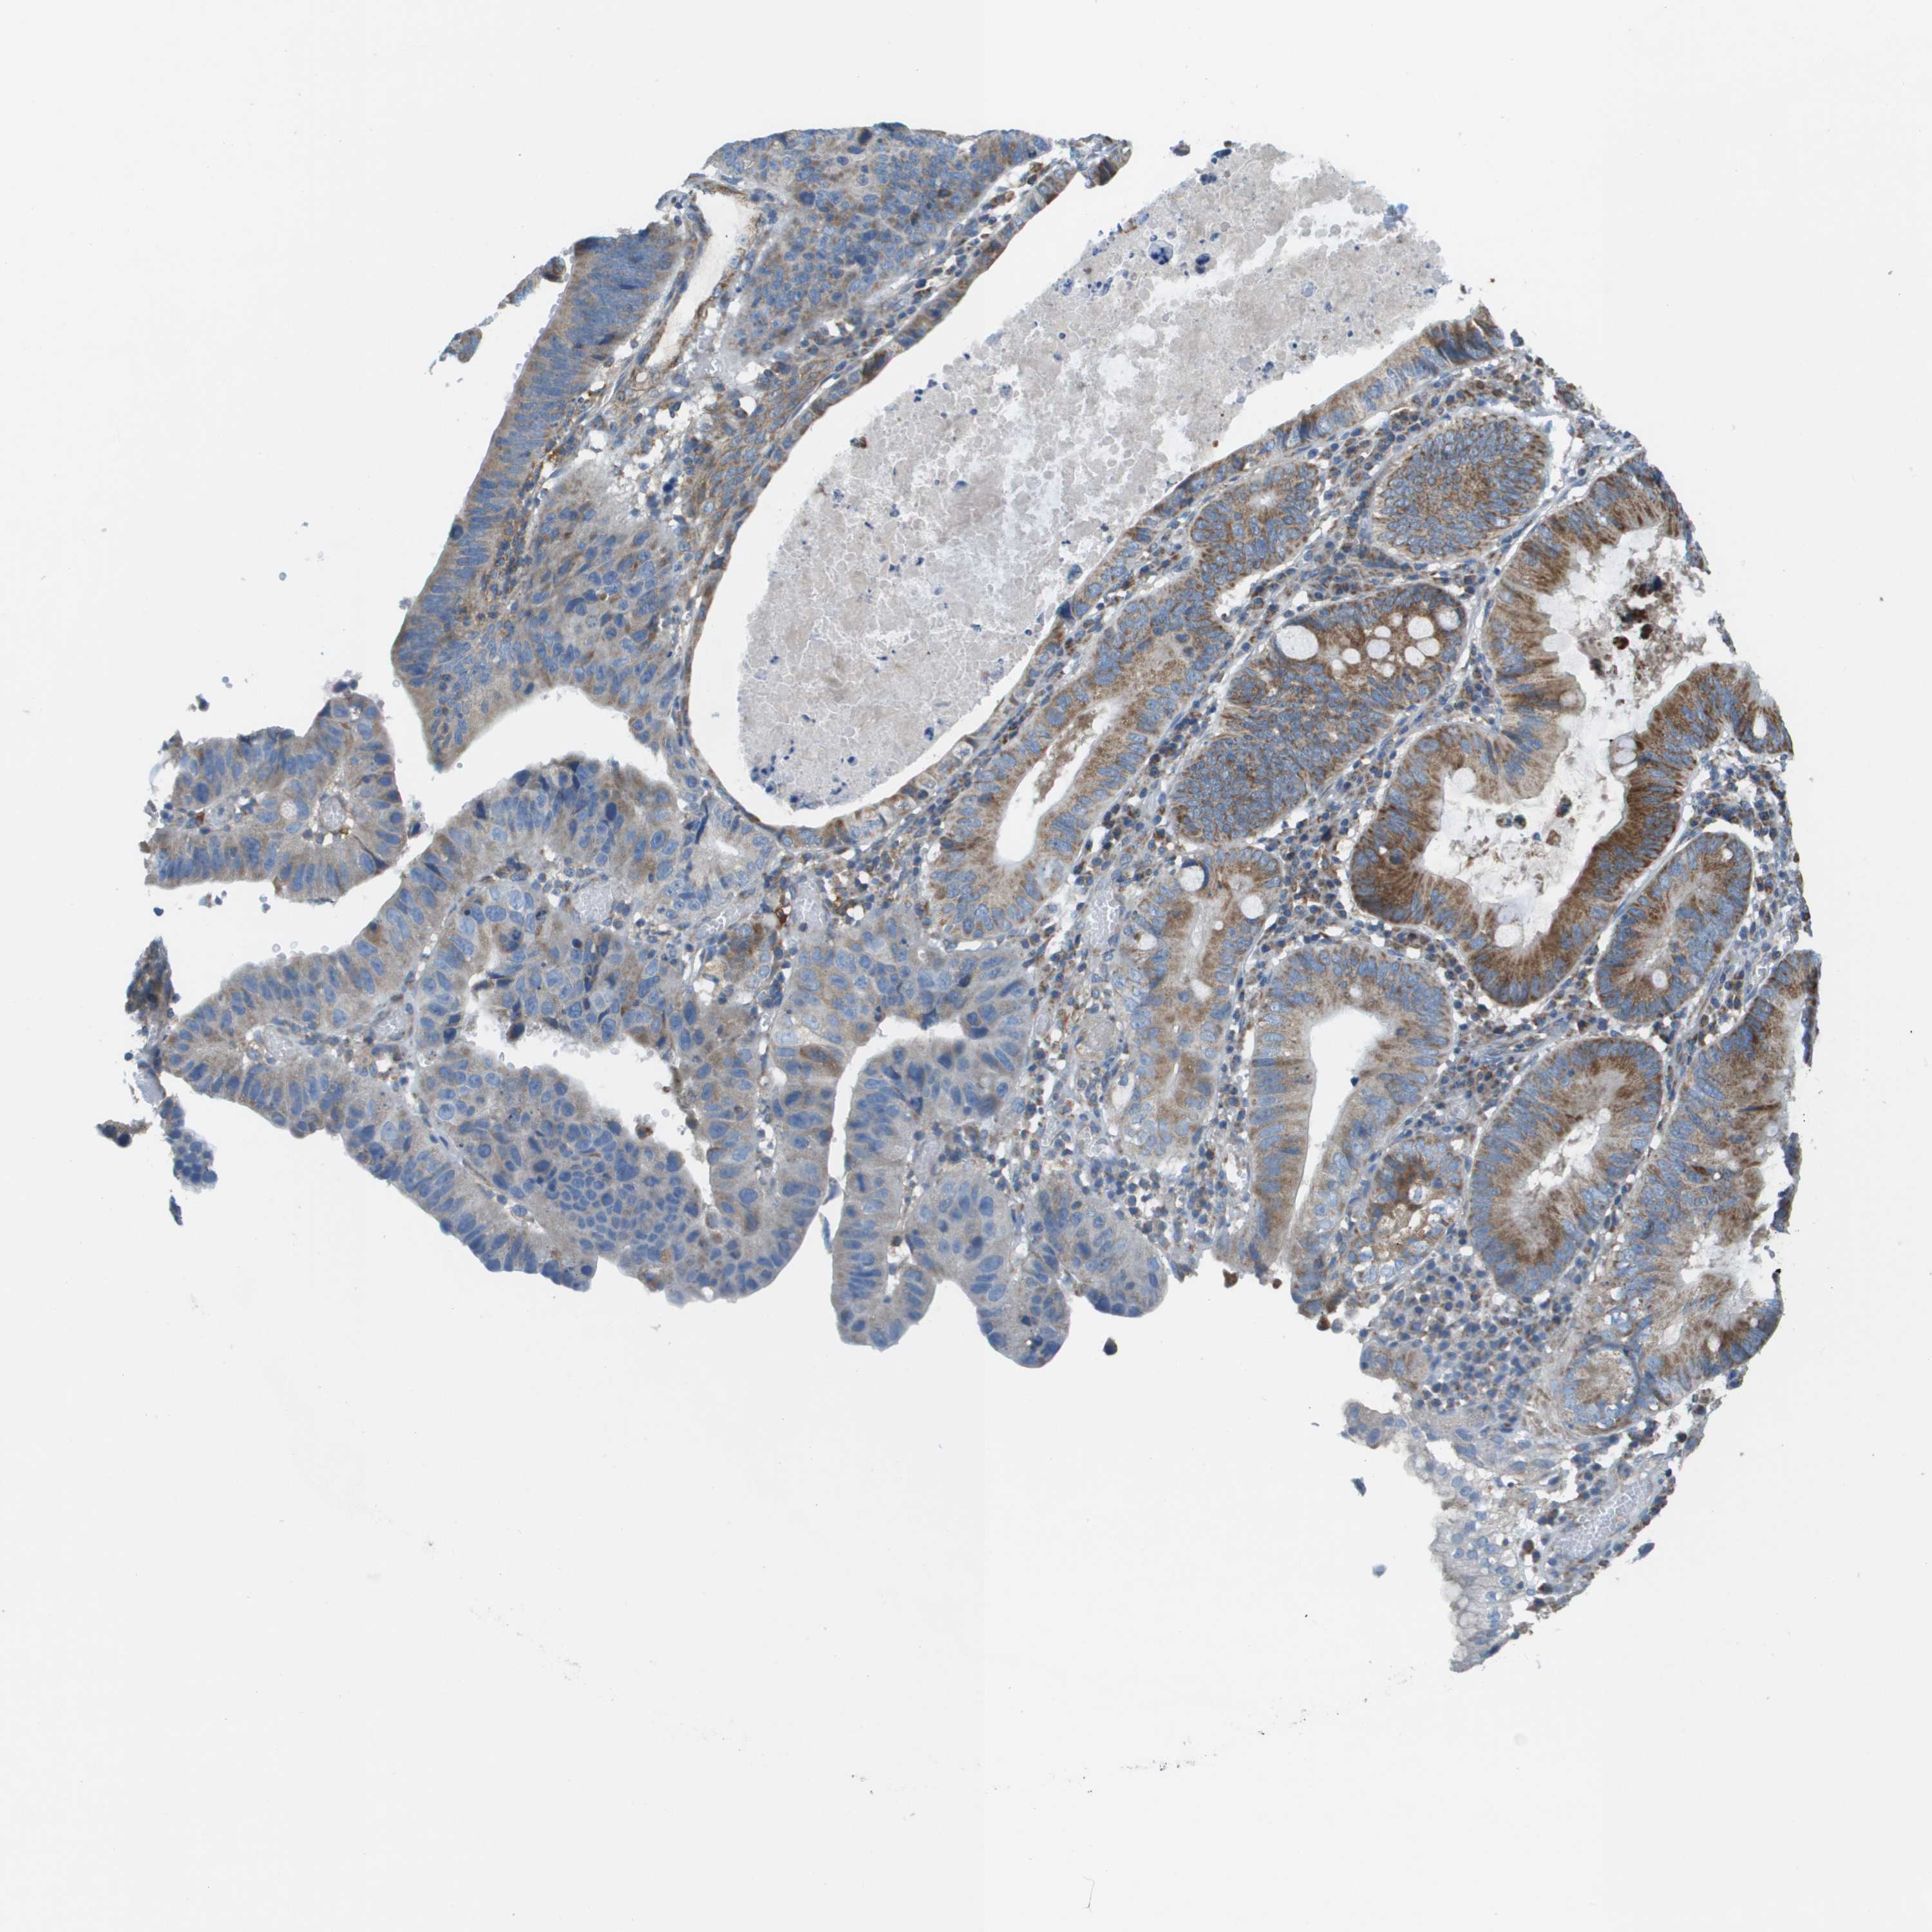

STOMACH CANCER - Protein expressioni

A mouse-over function shows sample information and annotation data. Click on an image to view it in a full screen mode. Samples can be filtered based on level of antibody staining by selecting one or several of the following categories: high, medium, low and not detected. The assay and annotation is described here.

Antibody stainingi

Antibody staining in the annotated cell types in the current human tissue is reported as not detected, low, medium, or high, based on conventional immunohistochemistry profiling in selected tissues. This score is based on the combination of the staining intensity and fraction of stained cells.

Each image is clickable and will lead to virtual microscopy that enables deeper exploration of all samples and also displays staining intensity scores, fraction scores and subcellular localization as well as patient and tissue information for each sample.

Antibody HPA017160

Staining

High

Medium

Low

Not detected

Intensity

Strong

Moderate

Weak

Negative

Quantity

>75%

75%-25%

<25%

None

Location

Nuclear

Cytoplasmic/membranous

Cytoplasmic/membranous,nuclear

Adenocarcinoma, NOS